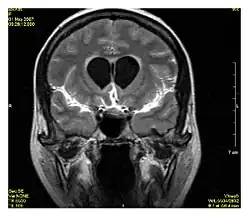

| Fluid-attenuated inversion recovery | FLAIR | Fluid suppression by setting an inversion time that nulls fluids | High signal in lacunar infarction, multiple sclerosis (MS) plaques, subarachnoid haemorrhage and meningitis (pictured).[15] |

| Double inversion recovery | DIR | Simultaneous suppression of cerebrospinal fluid and white matter by two inversion times.[16] | High signal of multiple sclerosis plaques (pictured).[16] |

Diffusion weighted

Diffusion MRI measures the diffusion of water molecules in biological tissues.[41] Clinically, diffusion MRI is useful for the diagnoses of conditions (e.g., stroke) or neurological disorders (e.g., multiple sclerosis), and helps better understand the connectivity of white matter axons in the central nervous system.[42] In an isotropic medium (inside a glass of water for example), water molecules naturally move randomly according to turbulence and Brownian motion. In biological tissues however, where the Reynolds number is low enough for laminar flow, the diffusion may be anisotropic. For example, a molecule inside the axon of a neuron has a low probability of crossing the myelin membrane. Therefore, the molecule moves principally along the axis of the neural fiber. If it is known that molecules in a particular voxel diffuse principally in one direction, the assumption can be made that the majority of the fibers in this area are parallel to that direction.

The recent development of diffusion tensor imaging (DTI)[43] enables diffusion to be measured in multiple directions, and the fractional anisotropy in each direction to be calculated for each voxel. This enables researchers to make brain maps of fiber directions to examine the connectivity of different regions in the brain (using tractography) or to examine areas of neural degeneration and demyelination in diseases like multiple sclerosis.

Another application of diffusion MRI is diffusion-weighted imaging (DWI). Following an ischemic stroke, DWI is highly sensitive to the changes occurring in the lesion.[44] It is speculated that increases in restriction (barriers) to water diffusion, as a result of cytotoxic edema (cellular swelling), is responsible for the increase in signal on a DWI scan. The DWI enhancement appears within 5–10 minutes of the onset of stroke symptoms (as compared to computed tomography, which often does not detect changes of acute infarct for up to 4–6 hours) and remains for up to two weeks. Coupled with imaging of cerebral perfusion, researchers can highlight regions of "perfusion/diffusion mismatch" that may indicate regions capable of salvage by reperfusion therapy.